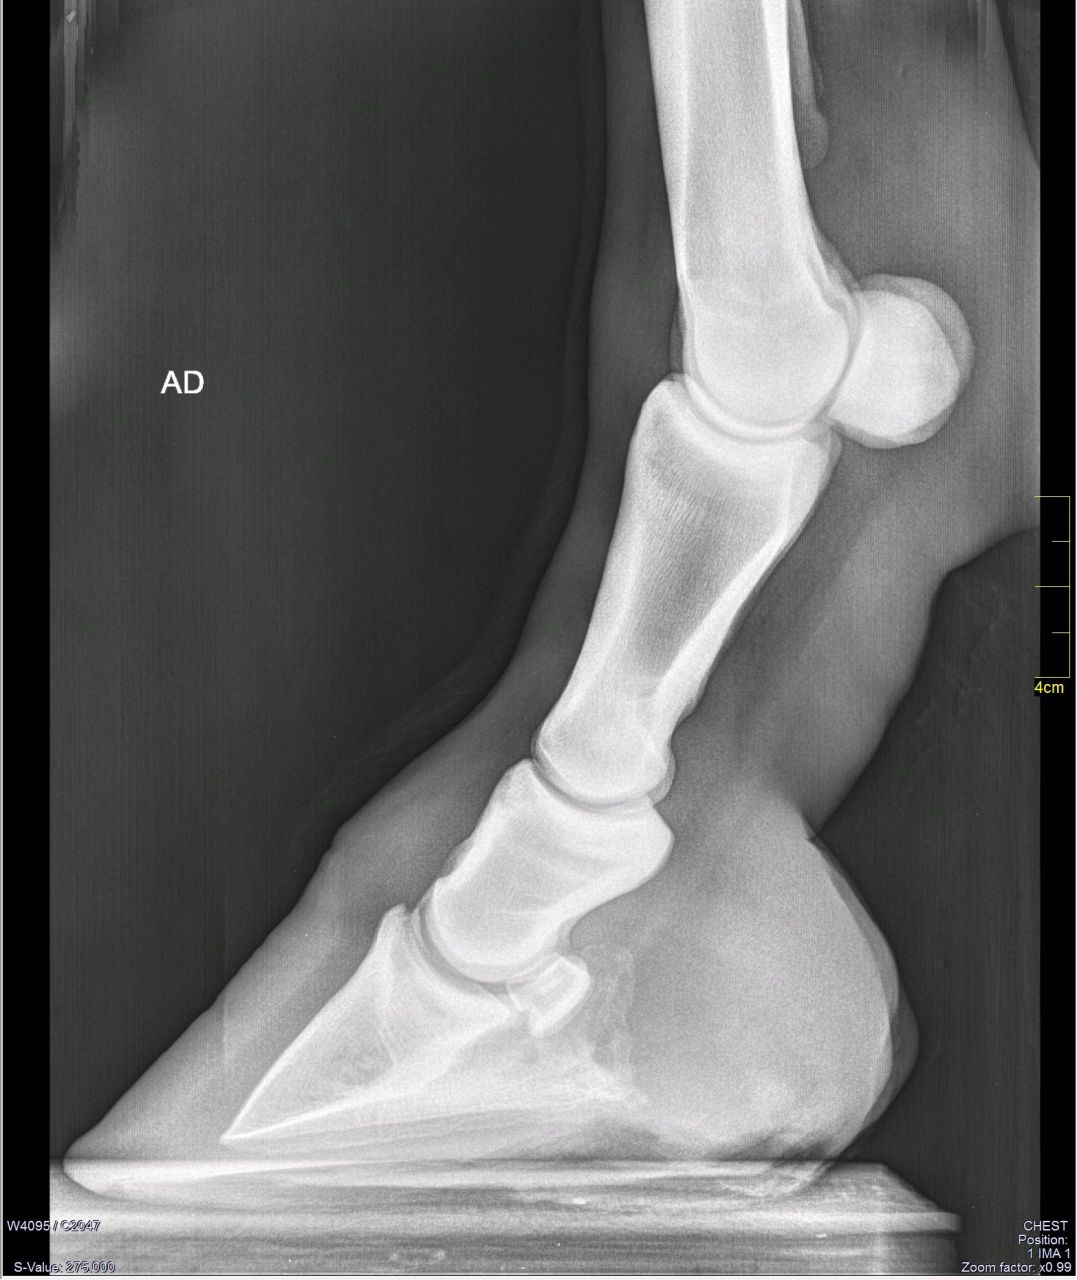

| Dire merci | swann, je trouve ça plus objectif de ne rien dire. Ma jument est très sensible mais déferrée depuis 6 mois après 16ans de ferrure et mauvais pieds. Et depuis quelques semaines, boiterie. Antérieur droit prononcé pour moi, "pas franc" d'après véto qui ne voit que la sensibilité du pied. La jument prend spontanément trot et galop sur sol hyper confort mais boiterie visible (pas que par moi). |

DéconnectéDire merci | Ben je dirais que la sole est (trop) fine et sans doute la ligne blanche évasée car l'os n'est pas tout à fait parallèle à la paroi. |

Par juliedebert : le 03/06/16 à 17:37:24

| Dire merci | Je précise d'abord que je n'y connais RIEN en radios, et pas grand chose en anatomie non plus... mais il me semble que la 3e phalange n'est pas dans la bonne inclinaison ? La base n'est pas parallèle au sol et l'avant semble plonger un peu. Début de basculement ??? (me tapez pas si je dis une connerie, il parait que les nuls peuvent participer ) |

| Dire merci | Alors, oui début de bascule de P3 qu'on remarque effectivement en regardant le parallélisme avec la paroi. Trop longue en pince, paroi pas dans l'axe du bourrelet corronal. Sole trop fine et on voit l'absence de concavite aussi. La jument a fait un épisode grave de fourbure ya 11ans. Je pense que ce sont les traces de cette fourbure mal soignée (pieds horribles depuis,déferrée ya 6 mois avec une transformation du pied assez spectaculaire c'est vous dire d'où on vient...) . Les vétos concluent naturellement à un épisode aiguë de fourbure, je ne peux pas l'écarter et je soigne en tenant compte de ce diagnostic. Cependant je pense pour ma part qu'il y a un autre probléme, car la boiterie est sur l'anterieur droit. La sensibilité s'explique par le manque de sole, le mauvais alignement de la phalange etc... Mais pourquoi une boiterie à droite ? Les vétos ne cherchent pas plus loin. Du coup je me demandais si certains verraient autre chose à creuser. Ça ressemble à quoi de l'arthrose ? Elle a 20ans |

| Dire merci | Pour une jument de 20 ans, elle a encore les superficies articulaires en bon état. Après c'est ce que je disais dans mon précédent message, s'ils veulent faire des mesures fiables avec un LM qui est oblique ... Mais bon.. a 20 ans? Mais je ne comprends pas ton interrogation sur la boiterie à droite, quand tu as le cliché qui te l'explique! |

| Dire merci | Radios prises dans un environnement idéal, au sec sur plat en bitume, jument parfaitement immobile. A la décharge de la veto: 20h30 après une journée de garde. Sur le compte rendu il est écrit: Sole de 2mm d'épaisseur sous P3 à ferrer en urgence. Et moi je fais marcher ma jument. Imaginez mon horreur devant cette info: 2mm. Ce n'est évidemment pas la vraie mesure, la sole reste trop fine mais 8mm. |

| Dire merci | Pour moi de base ta jument n a pas une sole trop fine. Elle es trop fine sous la pointe de p3 Mais remet p3 en place et tu as une sole ordinaire, pas épaisse à mort Mais pas degueu non plus |

| Dire merci | Pour moi de base ta jument n a pas une sole trop fine. Elle es trop fine sous la pointe de p3 Mais remet p3 en place et tu as une sole ordinaire, pas épaisse à mort Mais pas degueu non plus En gros tu viens de dire "c'est affreux, mais ça va" L'épaisseur de la sole est importante à l'endroit le plus fin, pas l'endroit le plus épais. Pour en revenir à la jument d' Aquarieum, peut être qu'elle tolère mieux la douleur d'un coté que de l'autre. Parfois on voit une boiterie à droite, on bloque le nerf, et pouf le cheval devient boiteux à gauche parce qu'en fait le problème est bilatéral mais plus marqué à droite. Enfin, tu as eu un diagnostique sur tes radios, et un conseil de ton véto, je ne sais pas ce que tu veux de plus? Ta jument est sensible des petons, elle a besoin de chaussures. Fers ou sandales, mais elle a besoin d'un peu plus de protection en l'état actuel des choses si tu veux continuer à bosser. Si tu peux te permettre de laisser ses pieds pousser sans rien lui demander (vu qu'apparement elle est confortable au pré) soit. Sinon il va falloir l'aider un peu jusqu'à ce que la sole ait retrouvé un peu d'épaisseur et la corne en muraille ait poussé suffisament pour que la partie décollée soit partie au parage. |